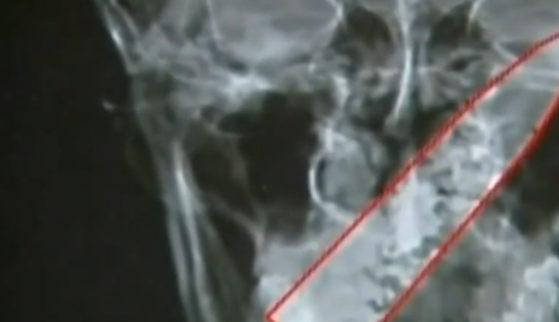

当时医生进行了初步的诊断,认为他可能是抽烟导致的。给丈夫开了一些药品,可是在吃完之后不光没有效果,反而越来越严重,因为头很痛,导致他只能按压自己的太阳穴,想要舒服一些可没有想到在经常按压之后居然让他吐血,马上又去了医院做了一个全身检查,可这一次医生却在他的大脑里面发现了金属物体。

让医生十分震惊的是,这个金属物体居然就是一把匕首,不过这个匕首的位置非常巧妙,避开了所有可能会毙命的地方,才让这个人能够活到现在,医生的建议是马上动手术,不过这个男人却犯了男人。他说自己并没有钱,医生也是出来了这个病人的难处,主动发的捐款。这个男人减免很大一部分的医疗费。大概三个小时手术之后终于是把这个匕首取了出来,这个男人也恢复到正常生活。

但是这个男人怎么着也想不起来自己为什么脑子里面会有一把匕首,他说自己的大脑基本上没有受过伤,在前些年都没有什么感觉,不过现在能够把自己的病给治好,其他的也不用想了,以后没有了病就可以好好的生活。